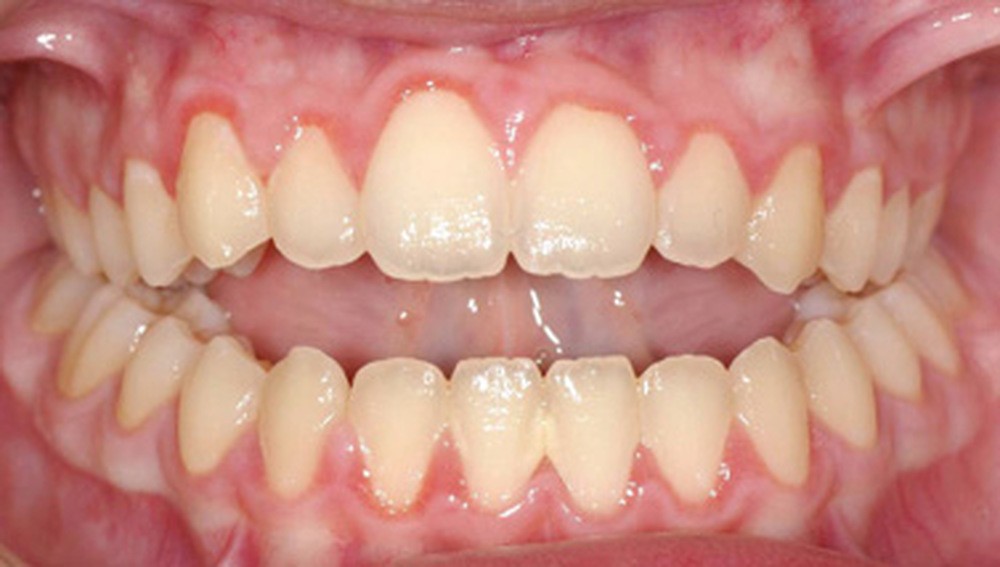

Quelques années plus tard, au moment de démarrer sa prise en charge orthodontique, la patiente présentait à nouveau une béance antérieure, un décalage des milieux incisifs de 2 mm et le problème transversal avait récidivé. Lors de l’examen clinique, elle présentait un inversé d’occlusion bilatéral postérieur et une ventilation buccale exclusive. À la suite du refus de réaliser l’amygdalectomie de façon précoce, elle ronflait toujours et sa déglutition ne s’était pas modifiée malgré des séances d’orthophonie (fig. 7 à 15).